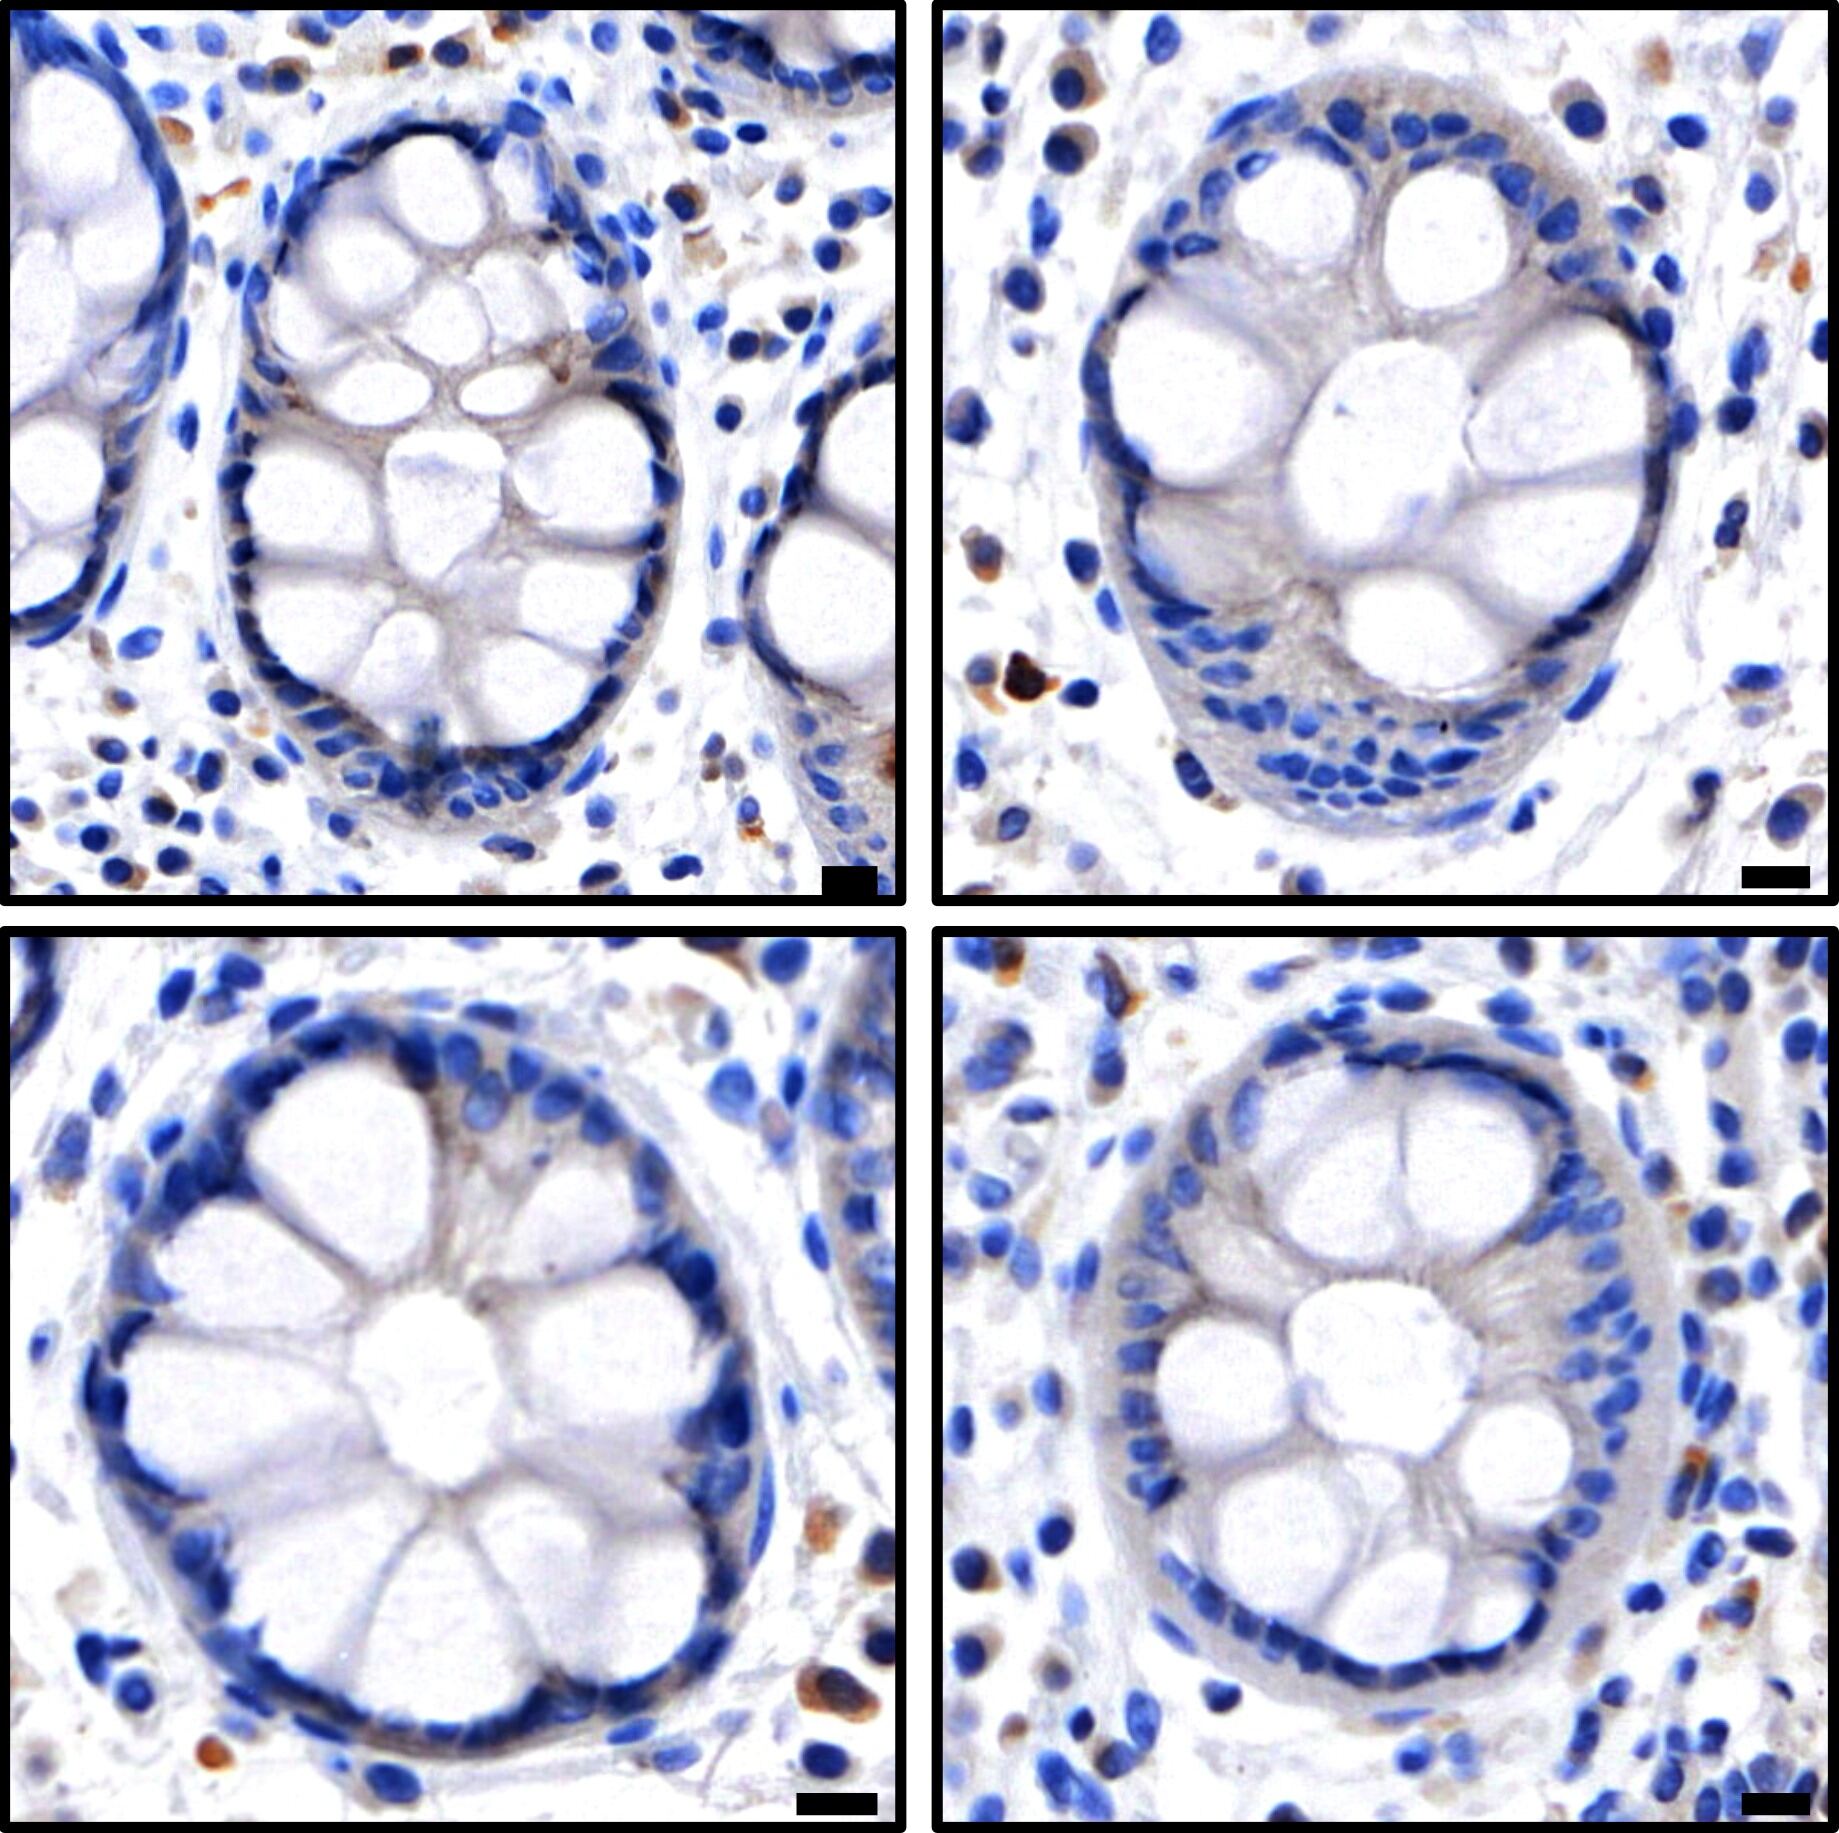

Atlas of necroptotic pathway expression in human intestinal crypts.  Credit: WEHI.

The team behind the study referred to their work as an “atlas of necroptosis” because it provides a precise map of which cells in the body are capable of undergoing necroptosis.

“We can now confidently visualise where and when necroptotic cell death can happen in the body,” said Prof Murphy.